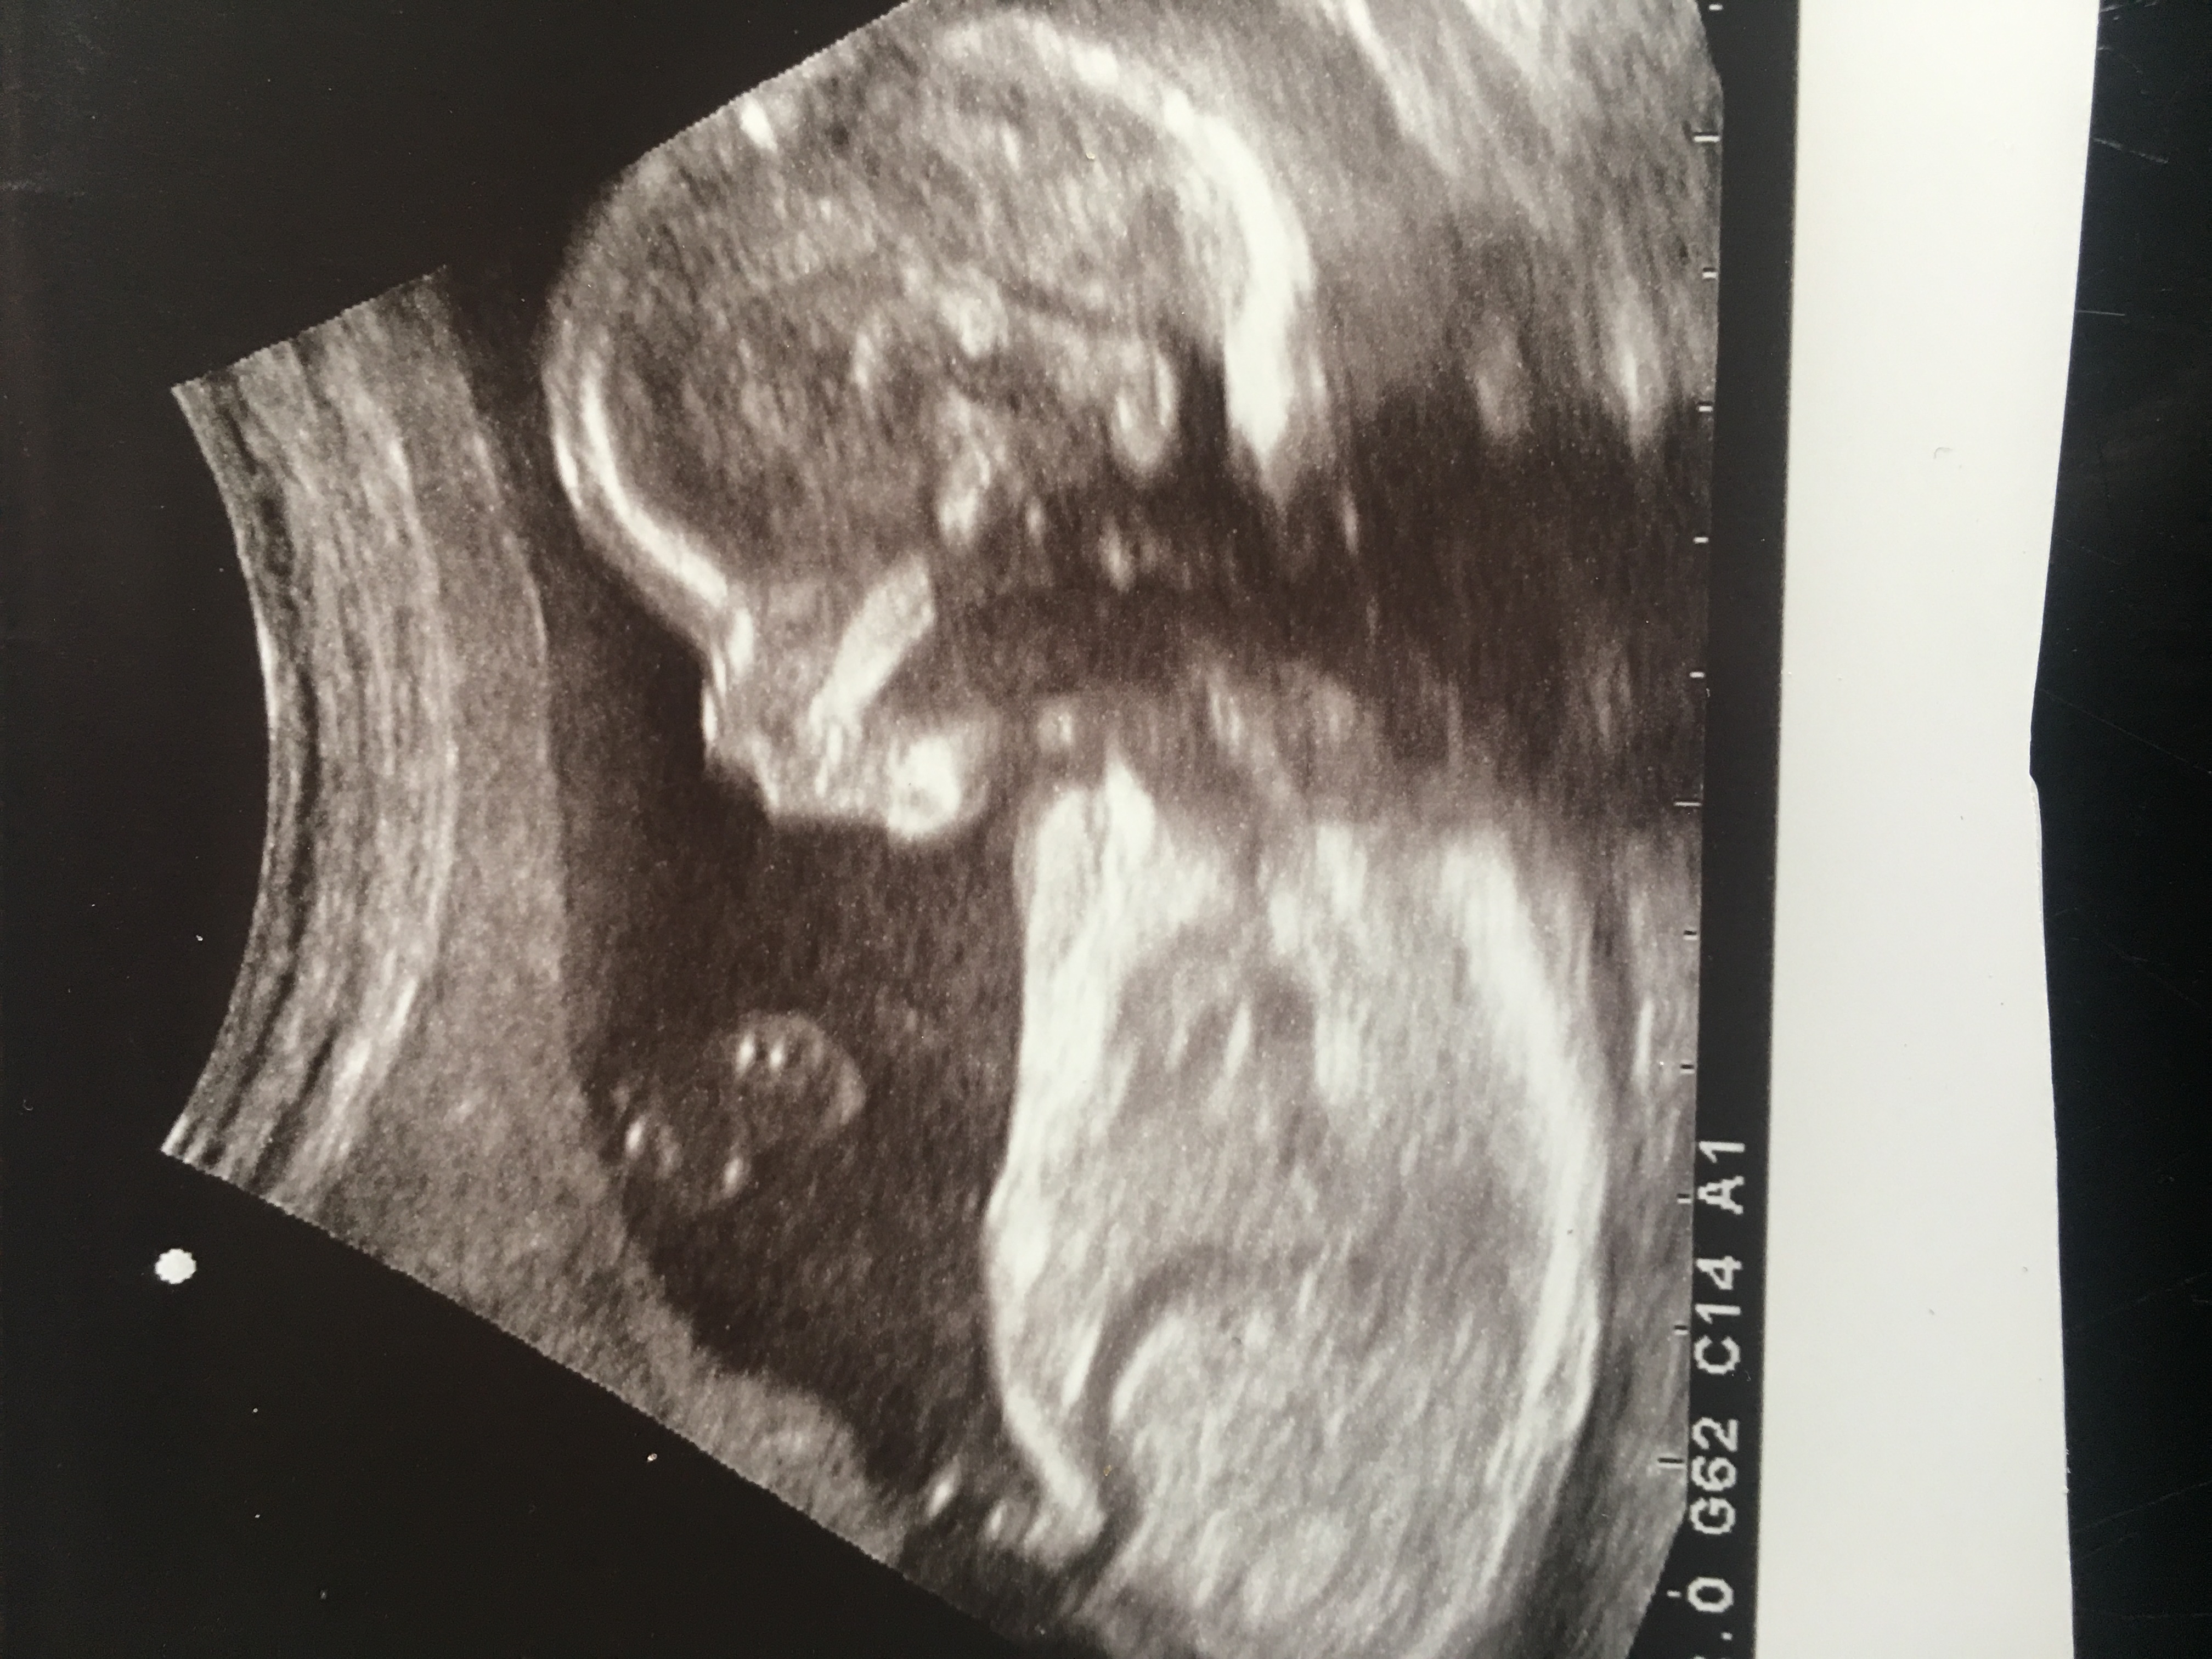

Potty shot indicates a girl what about baby’s skull please ?Attachment 39210

Attachment 39211 this is the potty shot I just really wanted a boy this time as it’s my last and I have all girls I’m actually not gender disappointed this time like last time but I was hoping baby was a boy 😂xx